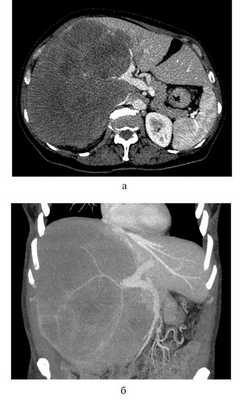

У одной пациентки 57 лет с местно-распространенной мультифокальной ВХК, вовлекающей ретропеченочный отдел НПВ, болезнь манифестировала болью в верхних правых отделах живота и синдромом нижней полой вены. Имеющиеся отеки нижних конечностей и нижней половины туловища уменьшались при положении больной на правом боку. У данной пациентки выявлено образование (ВХК, достигающая 34 см в наибольшем измерении) в V―VIII сегментах, распространяющееся на IV сегмент и хвостатую долю печени. Массив опухоли распространялся на ретропеченочный отдел НПВ (рис. 1). Рис. 1. Предоперационная К.Т. с контрастным усилением у пациентки с гигантской местно-распространенной внутрипеченочной холангиокарциномой, инвазирующей НПВ и правую ветвь ВВ. а ― в аксиальной плоскости; б ― коронарная томограмма. КТ ― компьютерная томография; НПВ ― нижняя полая вена; ВВ ― воротная вена. Во II и IV сегментах печени выявлены мелкие, менее 2 см, сателлитные очаги ВХК. Поскольку образование полностью замещало правую долю печени и распространялось на S4, объем остатка печени (S2, S3 и медиальная часть S4) составил 100%. При гепатобилиосцинтиграфии подтвержден адекватный функциональный резерв печени, позволяющий выполнить запланированное вмешательство в объеме расширенной правосторонней гемигепатэктомии.